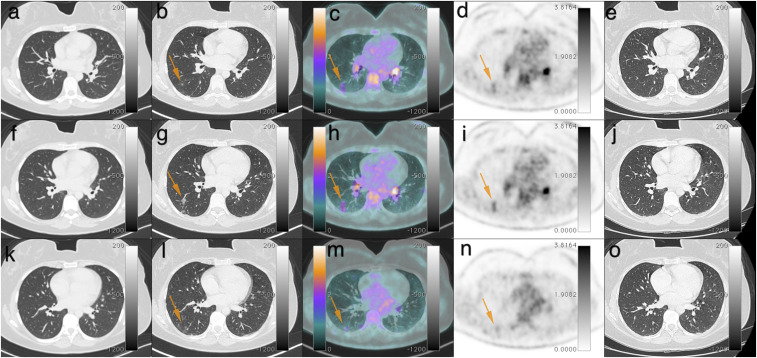

Figure 2.

Axial images of thorax computed tomography (CT) from February 13, 2020 (A, F, and K), axial thorax CT (B, G, and L), axial positron emission computed tomography/CT (PET-CT) fusion (C, H, and M), and axial PET (D, I, and N) from April 1, 2020, and axial thorax CT from May 18, 2020 (E, J, and O). PET-CT showed pulmonary opacities with ground-glass pattern in the right lower lobe that were not present in the previous CT, with mild 18F-FDG uptake. The last CT showed resolution of the opacities. This figure appears in color at www.ajtmh.org.

A 37-year-old woman with no comorbidities from Rio de Janeiro presented with mild afternoon fever, night sweating, and chest pain in February 2020 for 12 days. On February 13, 2020, a thorax computed tomography (CT) was requested and showed two irregular pulmonary opacities with central necrosis localized paracardially in the anteromedial basal segment of the inferior lobe in the left lung, the larger one measuring 2.2 × 2.0 cm, in addition to lymph nodes in the left hilum and minor pleural effusion in the same lung. She underwent investigation with several tests. Interferon-gamma release assay was negative, and the M band was positive for histoplasmosis in the immunodiffusion assay. She did not have a recent history of international travel. She started the treatment with itraconazole on February 19. The patient had a slow recovery, with recurrent fatigue and malaise. Six weeks after the beginning of the treatment, she presented recurring mild fever, fatigue, dyspnea, and chest pain. Her attending physician requested an 18F-fludeoxyglucose (18F-FDG) PET/CT for differential diagnosis between active histoplasmosis and lymphoma. The PET/CT was performed on April 1, 2020 and compared with the previous CT from February 13, 2020 (Figures 1, 2, and 3). A decrease in the dimensions of the pulmonary opacities previously identified in the left lower lobe was noted, but these opacities had significant radiotracer uptake (SUVmax 6.0). Positive lymph nodes were present in the cervical region (level IIa, bilaterally), mediastinum (subcarinal), left lung hilum, and hepatic hilum. These findings were consistent with inflammatory findings associated with histoplasmosis infection. Notably, other pulmonary opacities with ground-glass pattern that were not present in the previous CT were detected in the right lower lobe, with mild 18F-FDG uptake—SUVmax 2.5. These findings were highly suggestive for COVID-19. The attending physician and patient were informed of the possibility of COVID-19 infection, and the patient underwent an RT-PCR through nasal swab, which was positive for COVID-19. She observed the social distancing measures and was followed up by her assistant physician. The patient did not present severe symptoms and did not require hospitalization. She repeated the thorax CT on May, 18th for disease control. It showed resolution of the pulmonary opacities with ground-glass pattern in the right lower lobe. The irregular pulmonary opacities in the anteromedial basal segment of the inferior lobe in the left lung were still present but had additional decrease in its dimensions. The left hilum and subcarinal lymph nodes presented decrease in its dimensions as well. The minor pleural effusion in the left lung was not observed anymore. She has not repeated positron emission computed tomography/CT (PET-CT) until the present date.